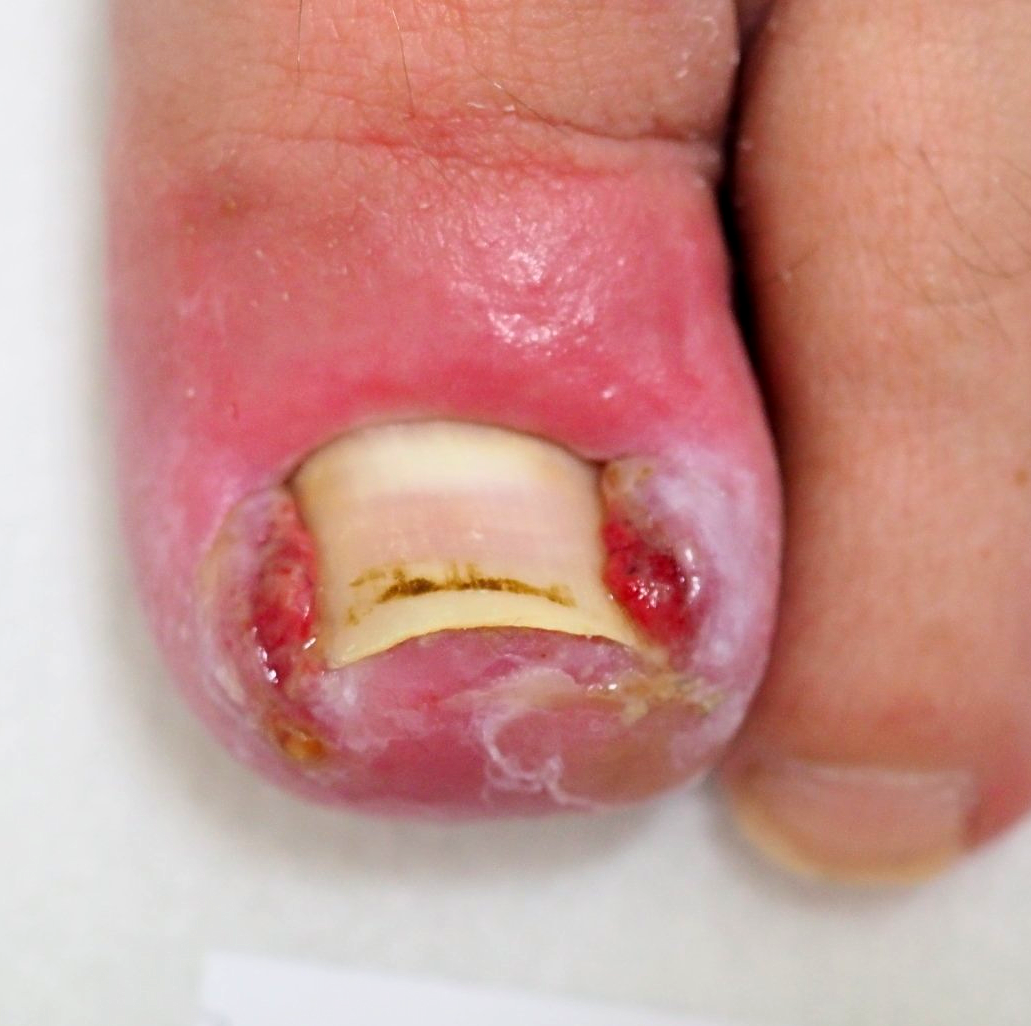

2.) Akutfall Hühnerauge

Hühnerauge subungual (unter der Nagelplatte)

Bild 1

die Ausgangssituation,

Bild 2

die geöffnete Nagelplatte unmittelbar nach der Entfernung des Hühnerauges